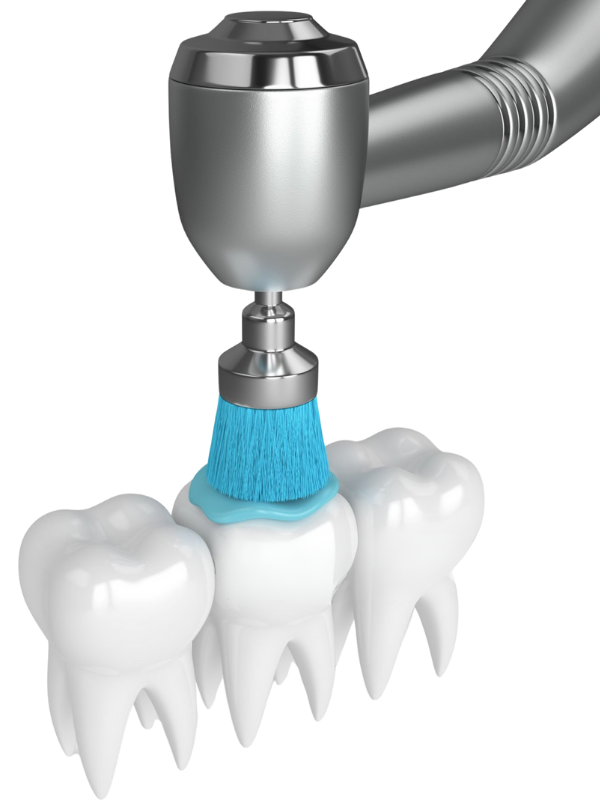

Détartrage, surfaçage ET POLISSAGE

POLISSAGE

Le blanchiment dentaire est un traitement esthétique qui vise à éclaircir la teinte des dents en éliminant les colorations dues au temps, à l’alimentation ou au tabac. Réalisé au cabinet ou à domicile sous supervision professionnelle, il permet de raviver l’éclat naturel du sourire en toute sécurité.